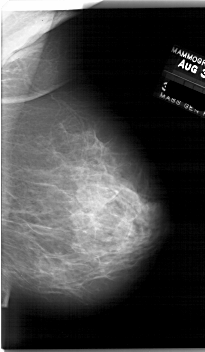

A_1761_1.LEFT_MLO

LEFT_MLO LINES 6271 PIXELS_PER_LINE 3886 BITS_PER_PIXEL 12 RESOLUTION 43.5 OVERLAY